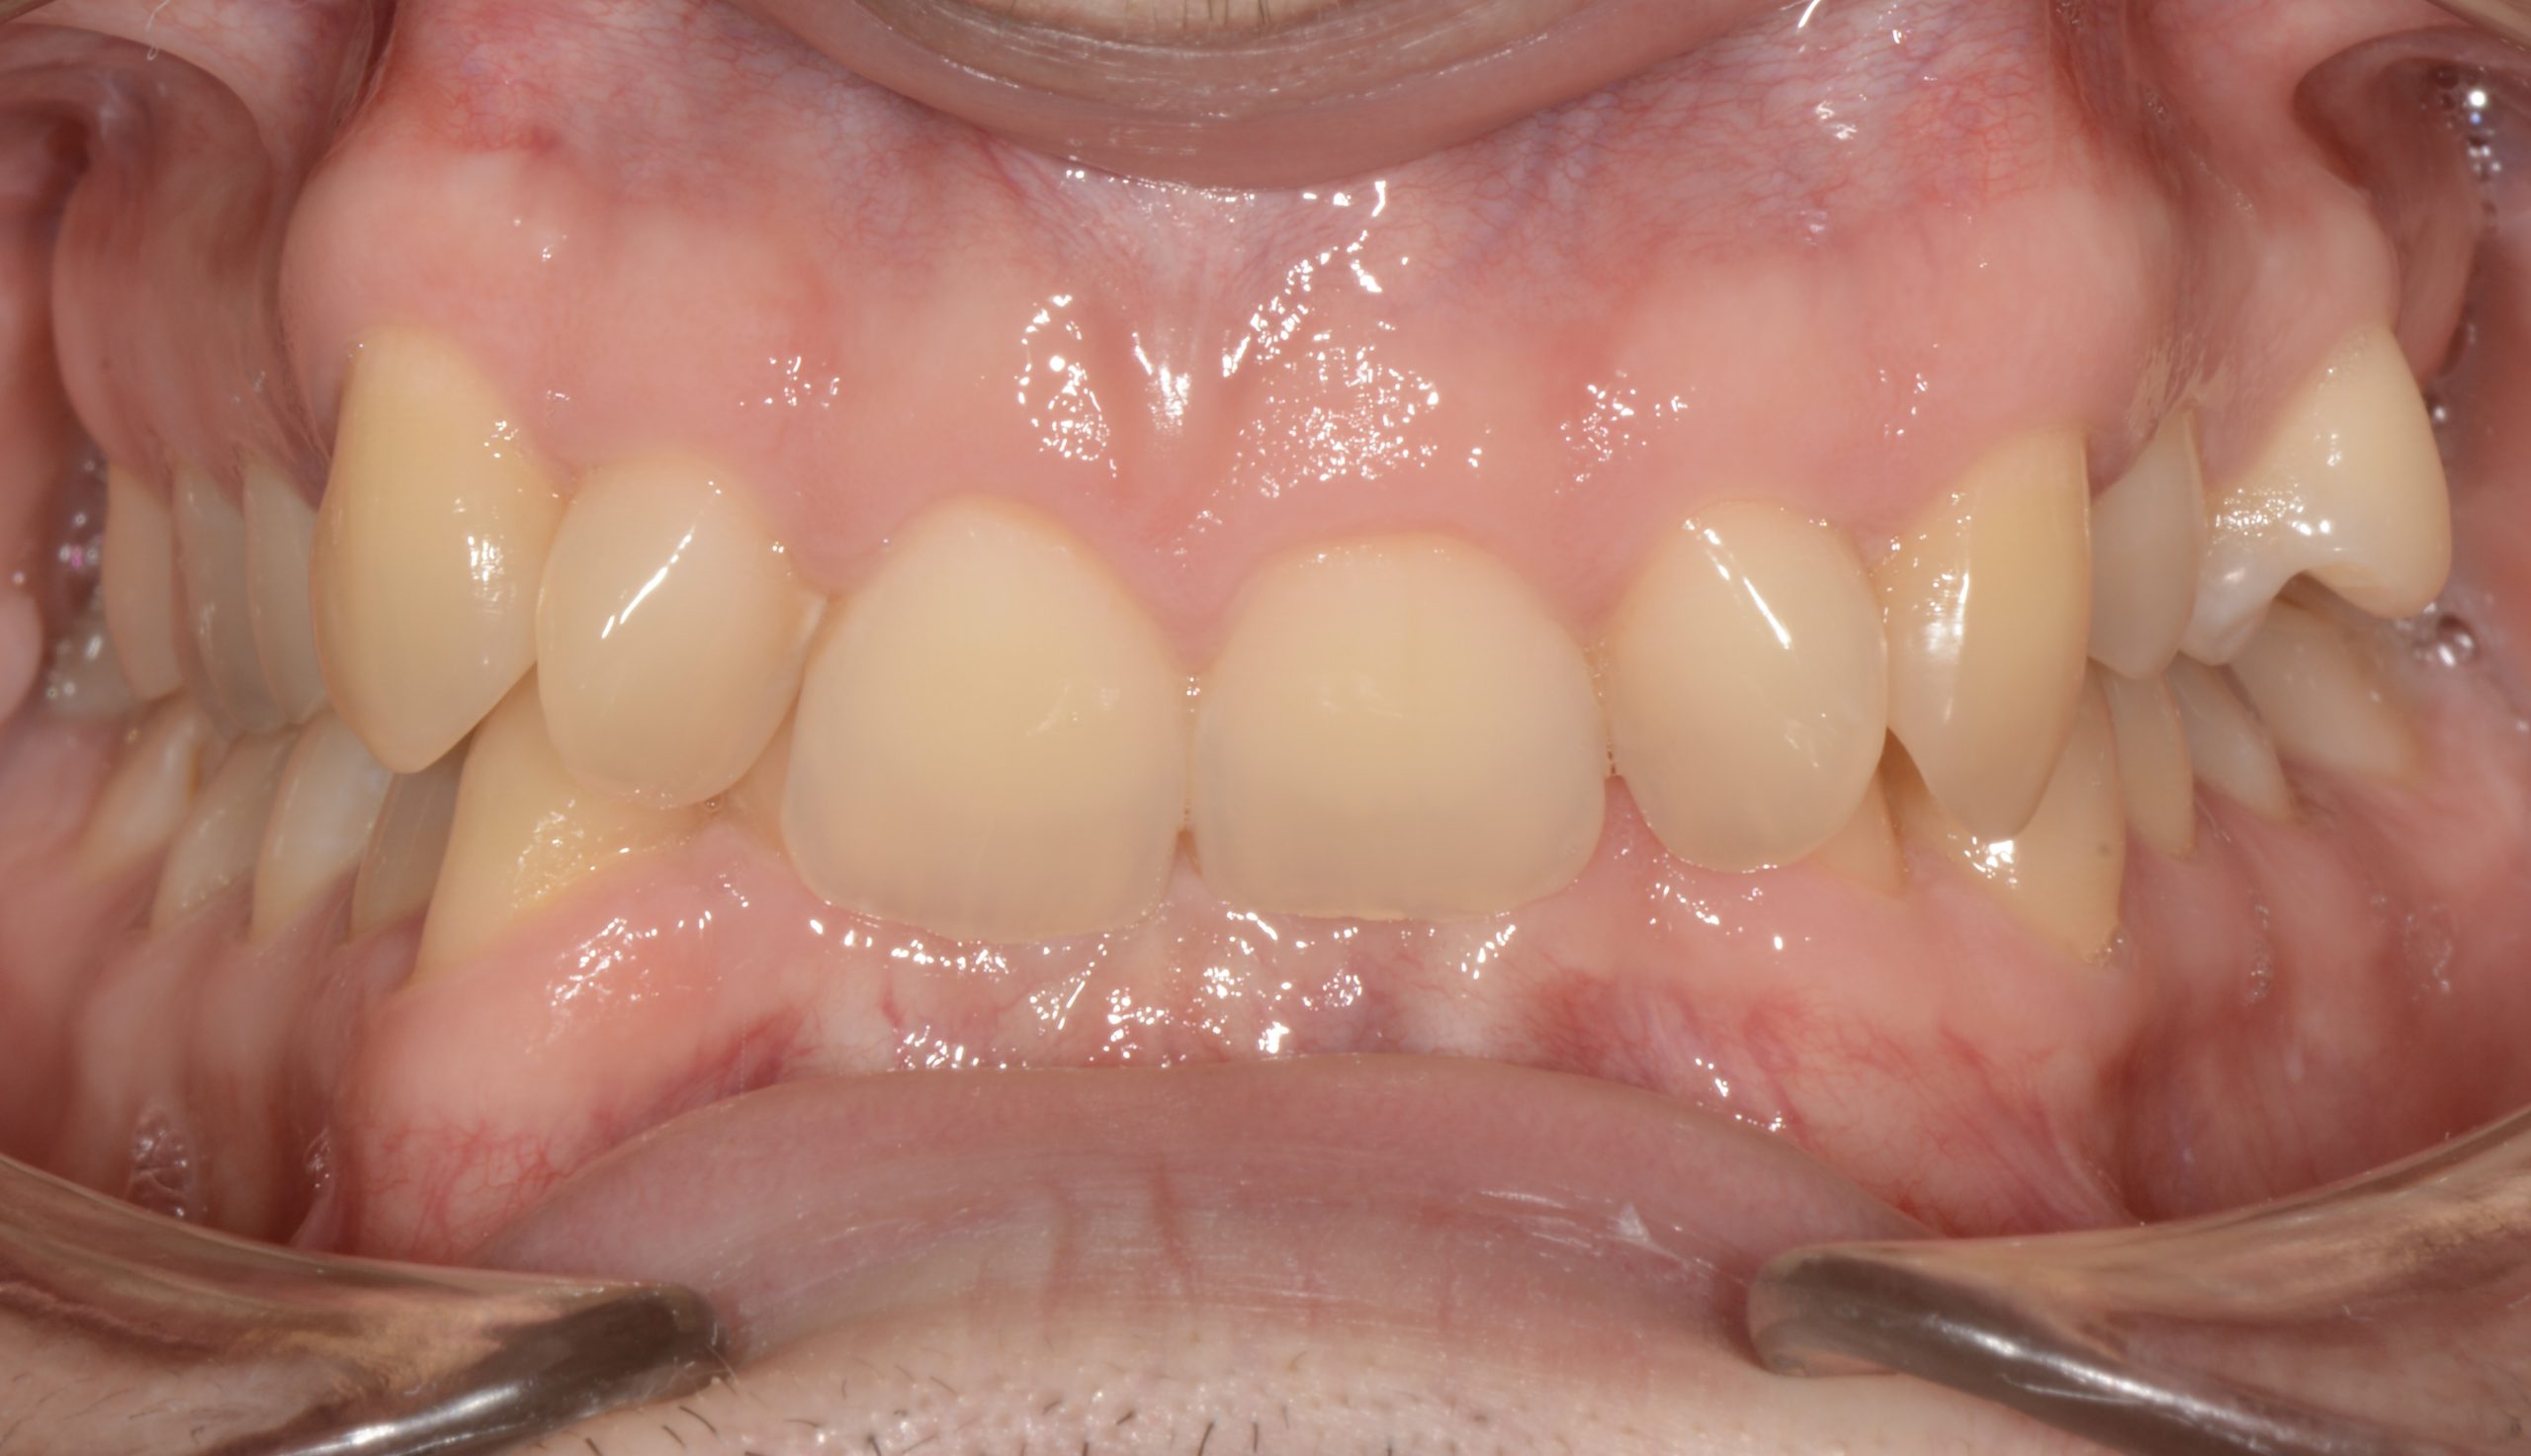

Az elmúlt évekből rengeteg szakmai referenciát tudnánk bemutatni, amelyek különböző fogszabályozási problémákat oldottak meg. Válogatva a több száz esetből, ezen az oldalon olyan képeket, információkat igyekeztünk bemutatni, amelyeknek a segítségével a jövőbeni pácienseinknek azt tudjuk üzenni: A Te fogsorod is lehet gyönyörű!

(Képeket a Pácienseink külön írásos beleegyezésével mutatjuk be!)